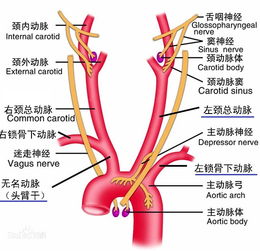

inferior mesenteric artery起源于腹主动脉,沿肠道分布,为肠道提供血液供应,该动脉在解剖学上具有复杂的分支,包括左结肠动脉、乙状结肠动脉等,这些分支进一步为肠道的各个部分提供血液,inferior mesenteric artery的解剖结构在人体内起着至关重要的作用,为肠道的正常功能提供了必要的血液供应。

inferior mesenteric artery在临床上具有重要意义,对于肠道疾病的诊断和治疗,了解inferior mesenteric artery的解剖结构和生理功能至关重要,医生可以通过观察inferior mesenteric artery的血液供应情况,判断肠道疾病的严重程度和预后,在手术中,医生需要了解inferior mesenteric artery的走行和分支情况,以避免在手术过程中损伤该动脉,导致肠道血液供应不足,进而影响肠道功能。

inferior mesenteric artery还与一些临床疾病的发生和发展密切相关,肠系膜下动脉综合征是一种由inferior mesenteric artery受压或阻塞导致的肠道血液供应不足的疾病,医生需要了解该病的发病机制和临床表现,以便及时诊断和治疗,一些肠道肿瘤和炎症性疾病也可能影响inferior mesenteric artery的血液供应,医生需要了解这些疾病的病理生理过程,以便制定合适的治疗方案。